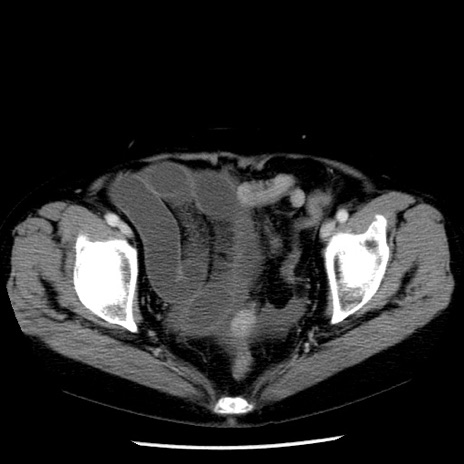

症例13(横断像)

【症例】70歳代女性

【主訴】腹痛、嘔吐

【現病歴】15時間程前(昨晩)より腹痛あり。今朝になっても症状の改善なく、嘔吐あり。腹痛も増悪あり、救急外来受診。

【既往歴】子宮癌全摘術後

【身体所見】意識清明、BP 121/72mmHg、P 74bpm、SpO2 100%(RA)、腹部:平坦・軟、腸雑音ほぼ聴取せず。下腹部・心窩部・臍左上に圧痛あり。反跳痛なし。

【データ】WBC 10600、CRP 0.15